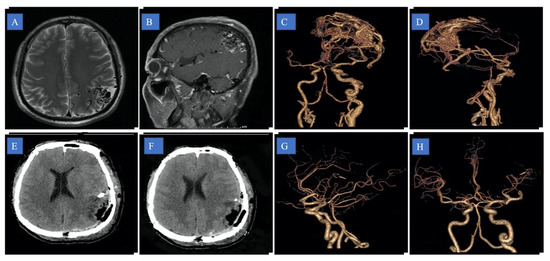

All patients received standard follow-up and evaluation of nervous system function after the operation. The incidence of bleeding after surgery, the complete disappearance of the disease as shown by imaging examination, (Figure 2 and Figure 3) and the existence of new and lasting neurological damage are the criteria for the results.

Figure 2. A 46-year-old man presenting with parietal cortex arteriovenous malformation (AVM), vertigo, and nausea. (A) Axial and (B) sagittal magnetic resonance image showing parietal cortex AVM; (C,D) pre-operative computed tomography angiography; (E,F) post-operative computed tomography; (G,H) post-operative computed tomography angiography.